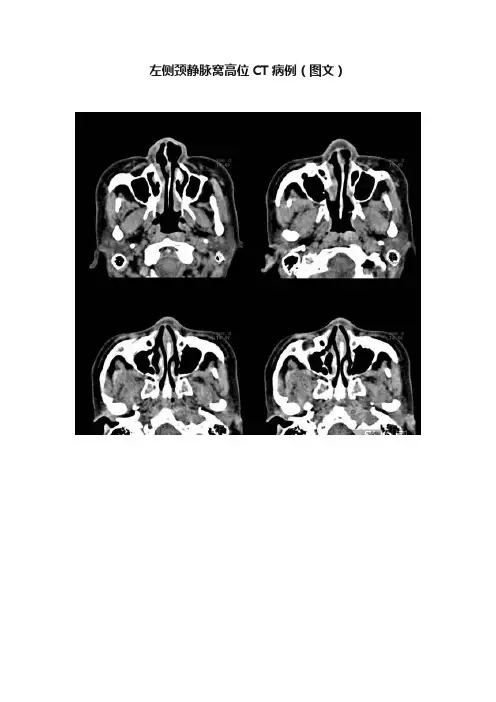

左侧颈静脉窝高位CT病例(图文)颈静脉窝内容纳颈静脉球,颈静脉球向上隆起与鼓室下壁毗邻。

正常情况下二者之间有一层骨板相隔。

颈静脉球有内移、外移、高位等解剖变异。

CT上正常颈静脉窝最多不超过蜗窗水平。

超过不一定有症状,但提示高位,在手术时应注意。

高位颈静脉球突入中耳腔可使鼓膜呈暗蓝色,容易误诊为颈静脉体瘤。

在中耳手术时容易误伤畸形的静脉球而引起不易控制的出血一、颈静脉球瘤1:颈静脉球瘤是起源于中耳和颈静脉孔区的非嗜铬性副神经节瘤,由上皮样化学感受器细胞组成,又称为化学感受器瘤。

二、高位颈静脉球是一种先天性变异;可表现为如本例:颈静脉窝扩大,内见软组织密度影(血管影),颈静脉窝边缘骨质光滑, 无破坏表现采用动态CT增强扫描或行颈静脉造影可以明确诊断.。